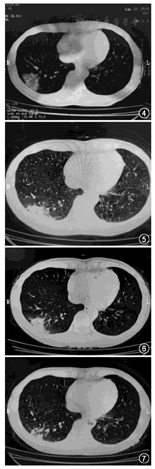

例2 患者女,42岁,有确诊病例接触史。1月15日起出现咳嗽,自行于家中服药,症状未见明显缓解且逐渐加重,咳嗽,久咳后可咳出黄绿黏液痰,咳时稍感胸痛、胸闷乏力等不适,1月22日行胸部CT确诊为疑似病例(图4),第3天出现发热、咳嗽、胸痛及呼吸胸痛,伴月经提前。1月24日收治入院,先后予以乳酸左氧氟沙星注射液、莫西沙星注射液静滴抗感染、予以利巴韦林注射液静滴、服用阿比多尔颗粒(1月30日起服用,服药3 d)。1月24日傍晚起开始服药,在基础方的基础上枸杞加量至15 g,蒲公英增至20 g,用法:水煎服(代煎),每天2~3次。

服药3 d后症状缓解,1月31日随访除感觉呼吸时稍有胸闷外无明显不适,2月2日随访稍感呼吸时"肺部深处有疼痛感",连续服药至2月2日。因个人原因2月4日暂停继续服药。2月7日病情好转出院,在基础方的基础上调整部分药物剂量加入陈皮、枳壳各10 g,带药5剂出院。2月8日电话随访,患者感全身乏力,但无其他不适,患者每日食用大枣5~6枚后,症状明显缓解,无其他不适。2月11日电话随访患者自觉良好。复诊CT显示感染灶吸收,部分肺组织纤维化,显效,见图5,图6,图7。

例3 患者男,37岁,有明确接触史。因反复发热,体温均低于38.5℃,伴胸闷、四肢乏力等不适,1月23日行胸部CT确诊为疑似病例(图8),1月25日晚开始服药,在基础方的基础上蒲公英增量至15 g,因药材原料缺乏问题,药材仅能使用3 d,1月29日药品服完,1月31日复诊,再次出现低烧。复诊CT见图9。因患者疗程不够,暂无法对疗效进行评估。